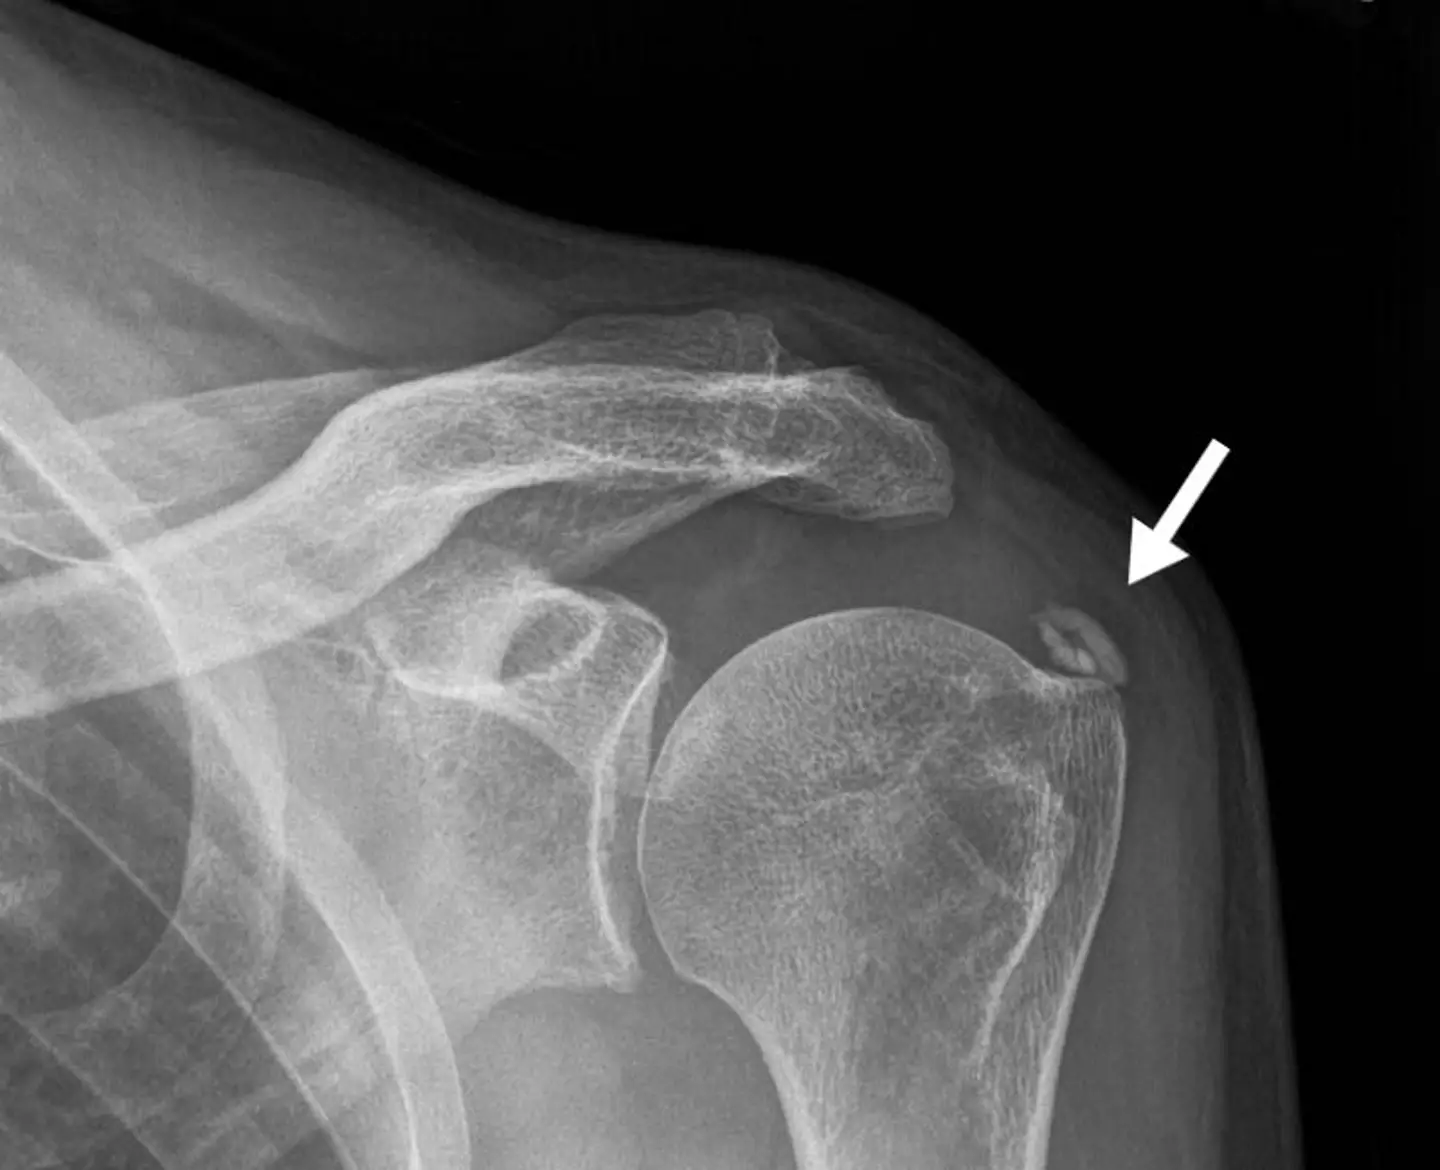

Calcium deposits can appear all over the body but are most commonly found on the skin or teeth, but can also be seen on shoulders and breasts, as well as internally on arteries, the brain and the kidneys.